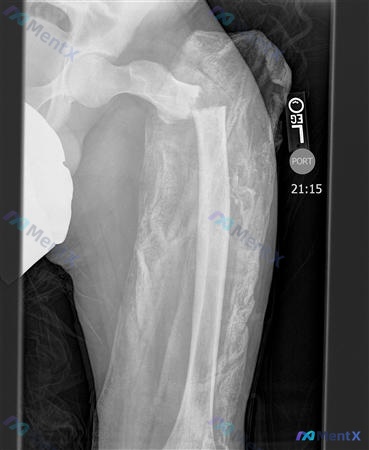

整理到一组5张X光片的读片资料,最初的问题是「图A至图E中哪一种最适合使用张力带固定原理」。 先不放结论,先看影像表现: 1. 大腿(侧位):股骨近端/转子下明显骨折,断端移位,股骨干皮质破坏、骨膜反应,周围多发斑片状高密度影及细碎骨片 2. 小腿(侧位):胫骨近端平台严重粉碎骨折,累及关节面,塌陷...